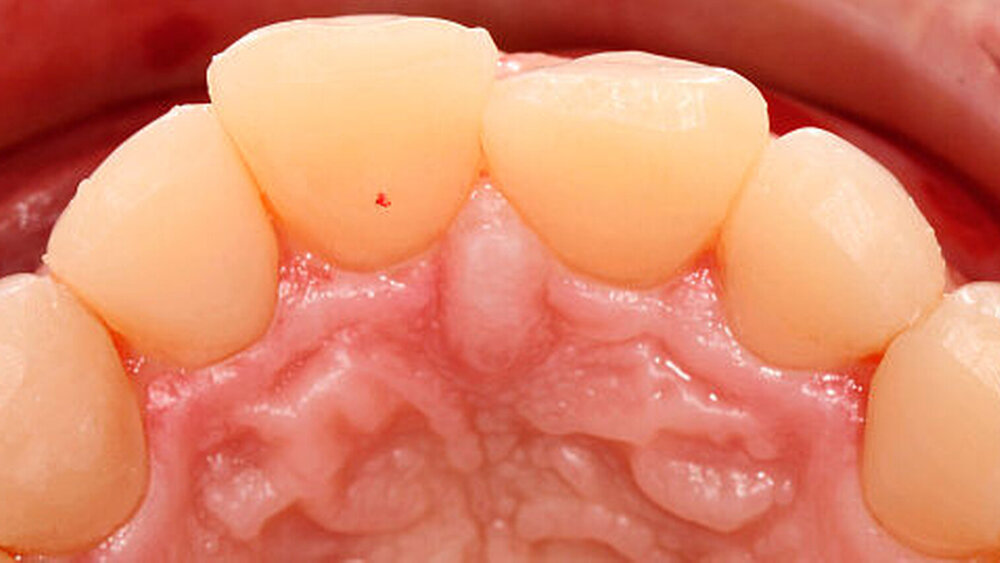

Nach diesen Vorarbeiten wurden Alginatabformungen von Ober- und Unterkiefer genommen und eine Bissregistrierung durchgeführt. Im zahntechnischen Labor wurde die ideale Okklusion im Artikulator bei einer Sperrung der Frontzähne um etwa einen Millimeter aufgewachst. Bei der Anfertigung der Wax-up-Modelle wurden jeweils die Frontzähne und Bereiche der endständigen Molaren nicht aufgebaut. Auf den Modellen wurden für Ober- und Unterkiefer je zwei stabile, lichtdurchlässige Übertragungsschienen hergestellt, die später im Mund der Patientin eine ausreichende Abstützung in der Front und in den nicht aufgewachsten distalen Bereichen gewährleisteten (Abbildung 2).